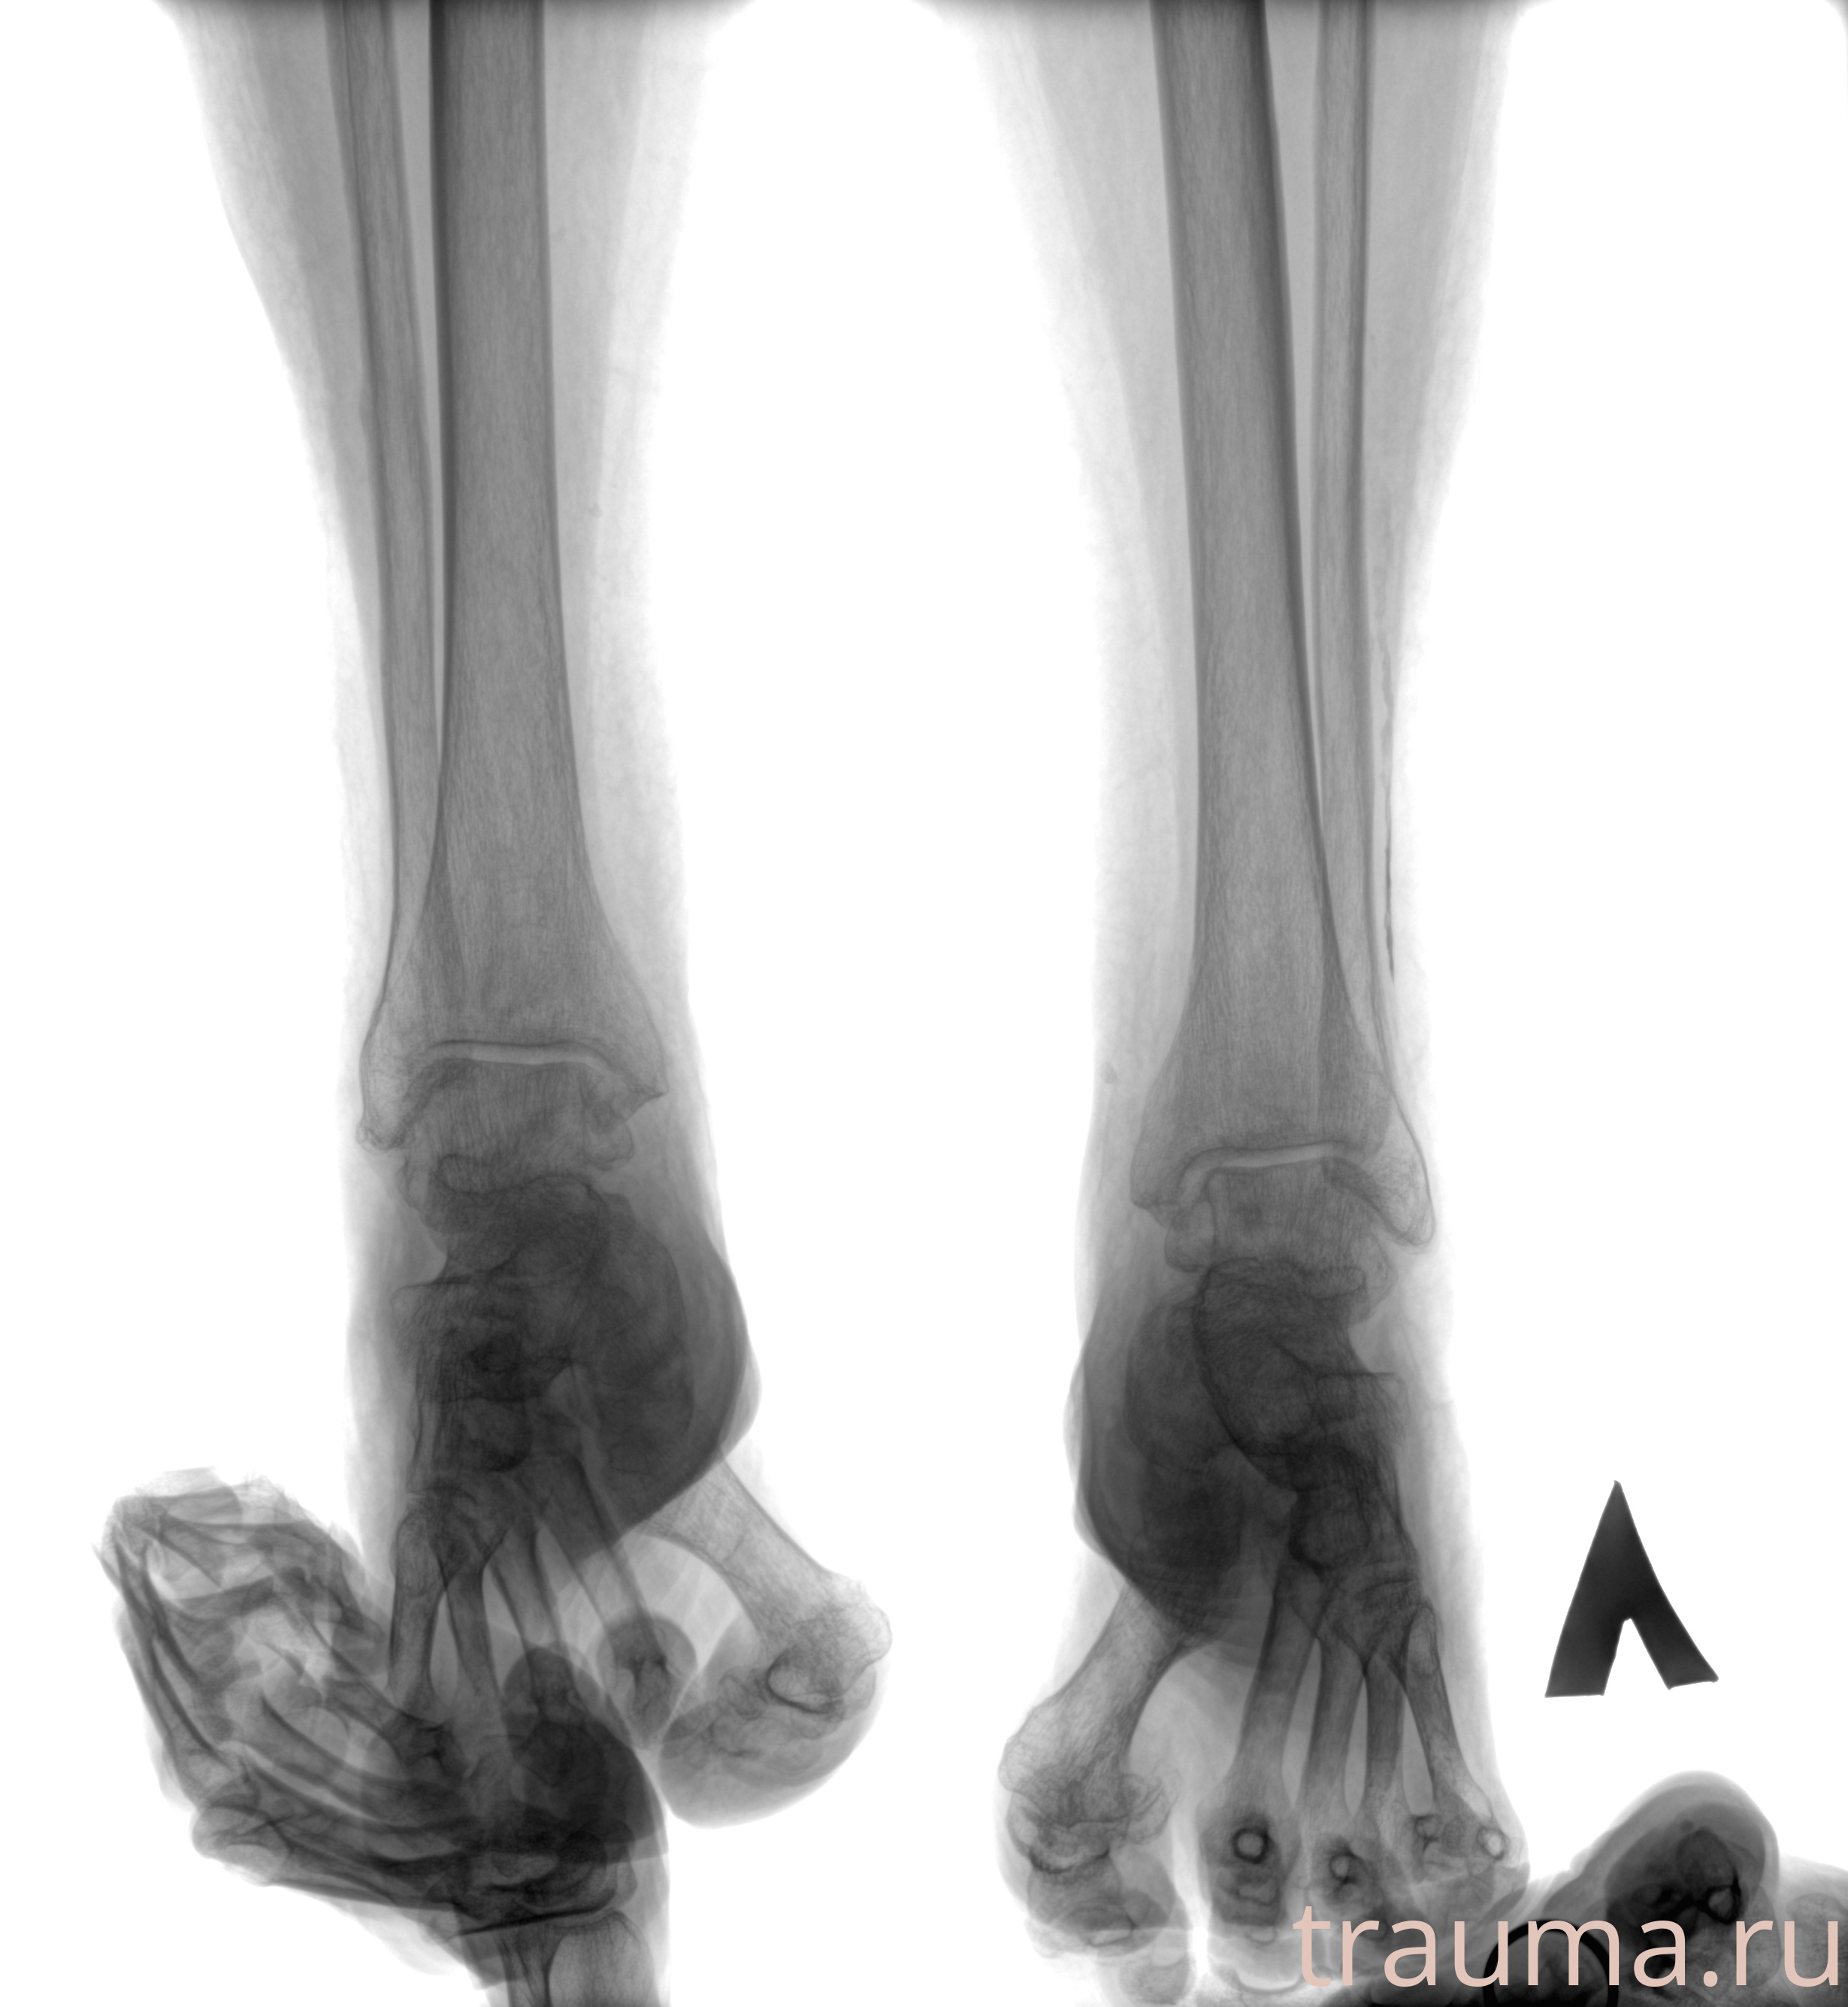

Рентгенограммы

Рентген на дому: по вашему адресу приезжает врач-рентгенолог, травматолог-ортопед с мобильным рентгеновским аппаратом, проводит диагностику травмы или заболевания, делает необходимые рентгенограммы, дает рекомендации по дальнейшему лечению. Получить качественные снимки в домашних условиях возможно благодаря уникальной методике, разработанной МосРентген Центром для института  Склифосовского